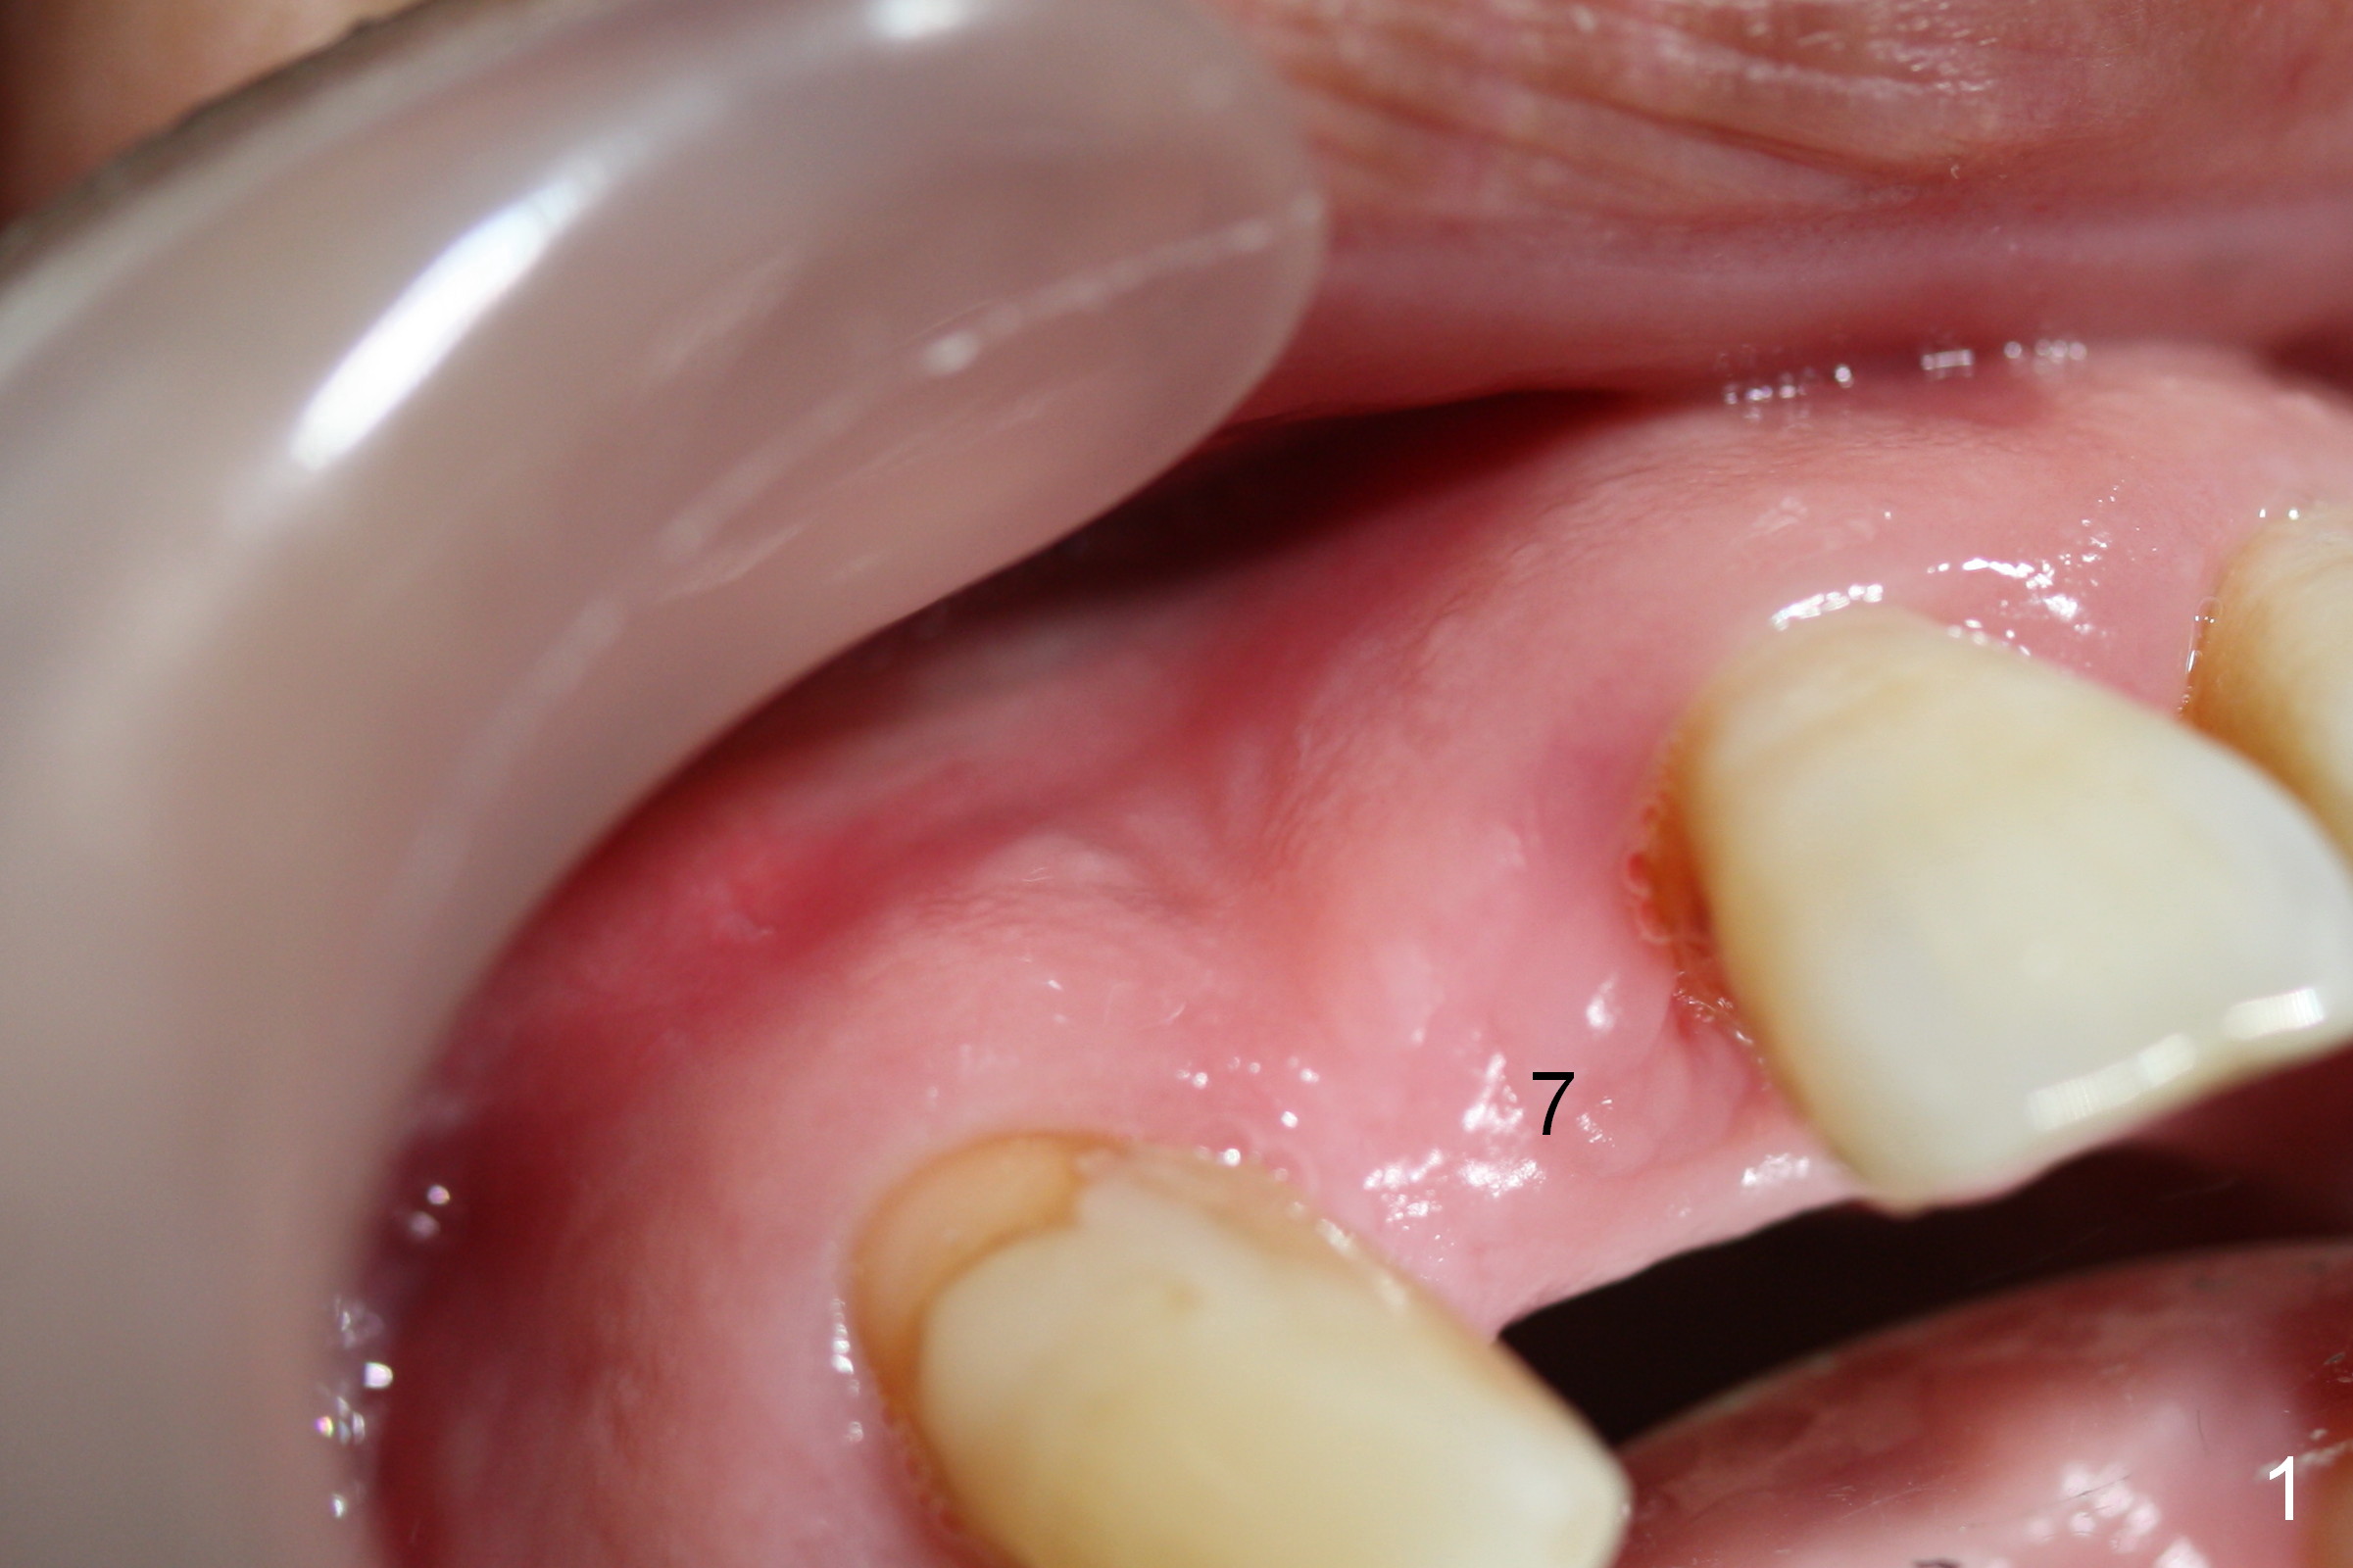

Apical Buccal Plate Perforation

Preop exam shows the apparent wide ridge at #7 (Fig.1). What is ignored preop is the concavity in the apical buccal region (Fig.2 *). When a 3x16(4) mm 1-piece implant is being placed (Fig.3 *, flapless), the apical buccal plate vibration is felt. The biggest mistake is that initial osteotomy is ~ 6 mm shy of the implant length, partially because of 6 mm gingival height. Since the tooth #6 is symptomatic after RCT with paste overfill (Fig.4 >), apicoectomy is contemplated at #6 with exploration of the buccal plate at #7 (Fig.5). Since the implant appears to be long enough, implant apical resection is performed (Fig.6). Since there is coronal thread exposure due to previous periodontitis (Fig.7 <), bone graft is placed in these 3 defective areas after decortication.